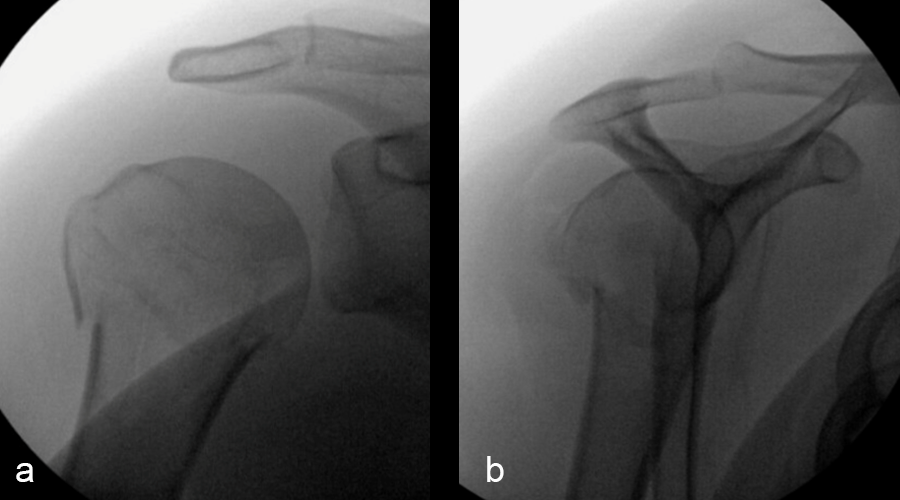

Three months after surgery, the patient had good elevation in the scapular plane to 130 degrees. External rotation was measured at 30 degrees, with more limited internal rotation (to the belt line). X-ray imaging (Fig 5) showed maintenance of fracture alignment and no change in screw position. The axial view (Fig 5c) highlights the subchrondral position of the variable angular screws in the humeral head. The patient was progressing nicely with functional tasks and adding weight in her therapy program.